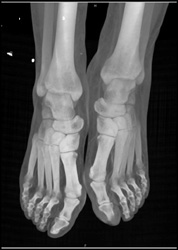

Humerus Fracture